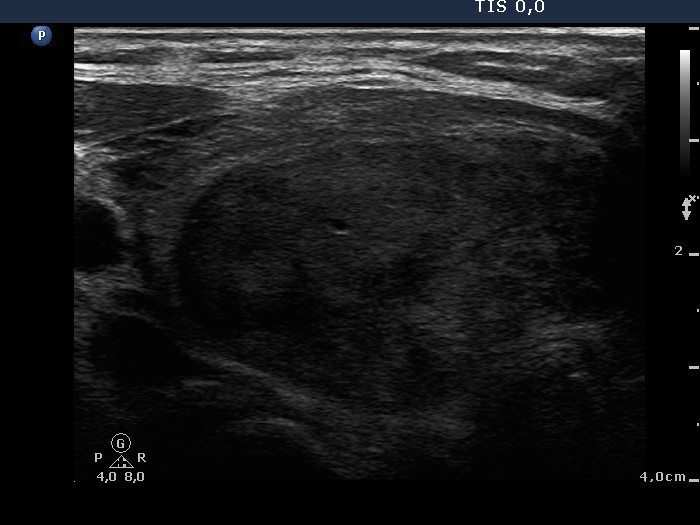

Ultrasonography: the thyroids were echonormal. There was an echonormal nodule occupying almost the entire right lobe. The lesion displayed a halo sign, cystic degeneration and presented perinodular blood flow.

5 sessions of sclerotherapy were performed. We demonstrate the 1st and 4th session.